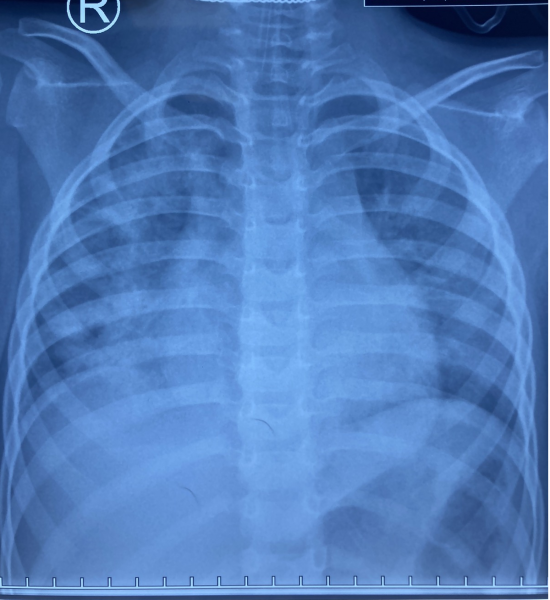

Ngày 20/5/2021 Khoa Cấp cứu Bệnh viện Nhi Đồng Thành Phố tiếp nhận một trường hợp trẻ Ng. D. Th. Q. 4 tuổi, nam, ngụ ở Trà Ôn, Vĩnh Long, được chuyển từ bệnh viện địa phương với chẩn đoán ngạt nước do té ao. Khai thác bệnh sử ghi nhận sáng cùng ngày nhập viện, Q. đang ở chơi trong nhà với mẹ, nhân lúc mẹ bé dọn dẹp nhà cửa không để ý đến, trẻ đi ra trước nhà chơi, không may té xuống ao nước phía trước nhà. Người nhà phát hiện, vớt trẻ lên, xốc nước và đưa trẻ đến bệnh viện địa phương trong tình trạng hôn mê, tím tái thở yếu, co gồng, được các bác sĩ cấp cứu đặt nội khí quản giúp thở, chống co giật, sau đó chuyển đến Bệnh viện Nhi Đồng Thành Phố. Tại đây, ghi nhận trẻ hôn mê, tím tái, co gồng từng cơn, Xquang ngực cho thấy phổi trẻ tổn thương nặng lan tỏa 2 phế trường, nên được xử trí thở máy thông số thích hợp, chống co giật, chống phù não, điều chỉnh nước điện giải, kiềm toan và cho kháng sinh phổ rộng điều trị viêm phổi hít. Hiện tình trạng trẻ còn nặng, được chuyển khoa Hồi sức tích cực điều trị tiếp.